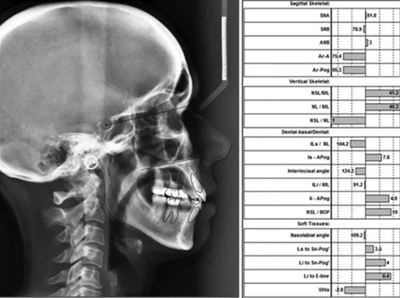

頭影測量分析,SNA角84°,ANB角6°,高角型,詳見下表。

患者側貌改善,下唇唇肌緊張消失,上下唇可自然閉合。磨牙及尖牙關系糾正至I類,覆合覆蓋正常。上下頜弓型糾正至卵圓形,牙弓寬度增加。頭影測量分析示SNA角81.8°,ANB角3°。頭影測量重疊圖示下頜骨向后旋轉,垂直面高度略有增加。